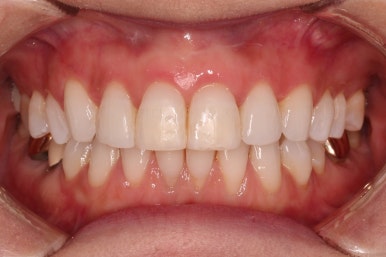

초진 시 입안의 모습입니다.

환자분이 원하셨던 부분은 윗니 작은 앞니가 하나 튀어나와서 개선하고 싶어하셨습니다.

부가적으로 아랫니 앞니가 마모가 심하여 높낮이가 달라보이는 점이었는데요.